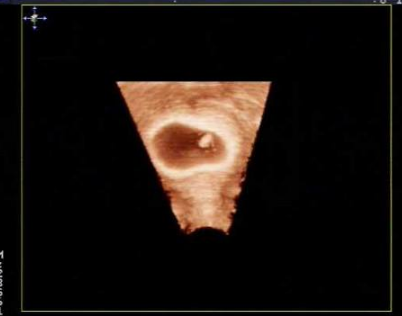

雙角子宮圖片

A:雙角子宮是子宮在發育過程中的一種畸形。子宮是由兩根副中腎管,在中間匯合而成,匯合之後,兩根副中腎管中間的組織,就會退化形成一個腔。但是如果發育過程中,匯合後中腎管的末端的中隔消失,但是上部未消失,就會在子宮上部形成兩個角,成為雙角子宮。雙角……

A:雙角子宮是一種子宮發育畸形的狀態,主要是患者子宮底部融合不完全導致的,患者進行B超或者是宮腔鏡檢查能夠發現子宮和正常女性相比不規則。嚴重的雙角子宮患者也有可能會伴有明顯的腹痛,或者來月經期間有痛經症狀。患者在懷孕時容易造成胎位不正,胎兒不能……